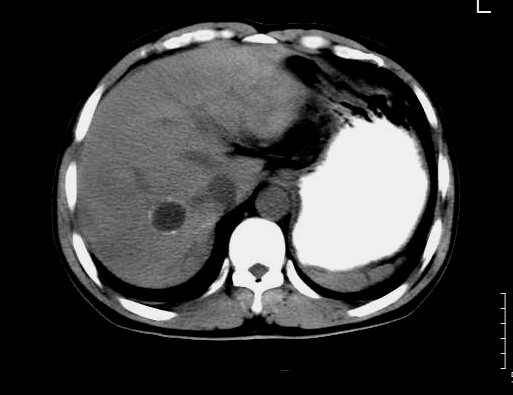

男,44岁,解黒便18天,胃镜:胃小角溃疡性质待查,表浅性胃炎。b超肝右叶占位。ct平扫肝右叶见一囊性占位,ct值:18hu,壁呈带状高密度钙化,增强扫描未见强化。考虑:囊肿?但壁钙化第一次见,不能确定,病人是南方石山地区,未到过牧区,能否排除包虫?

平扫ct值:

18hu.

增强扫描:病灶未强化。